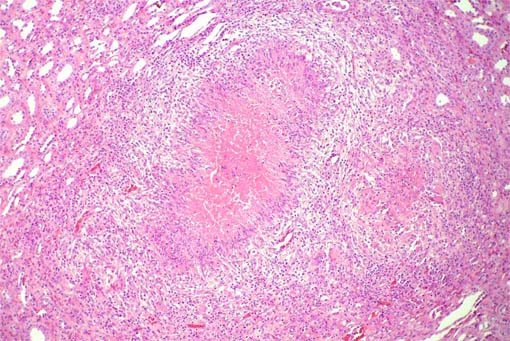

Los cortes histológicos revelan abundantes lesiones nodulares que

corresponden a los puntos blanquecinos identificados en la macro. H&E,

X100.